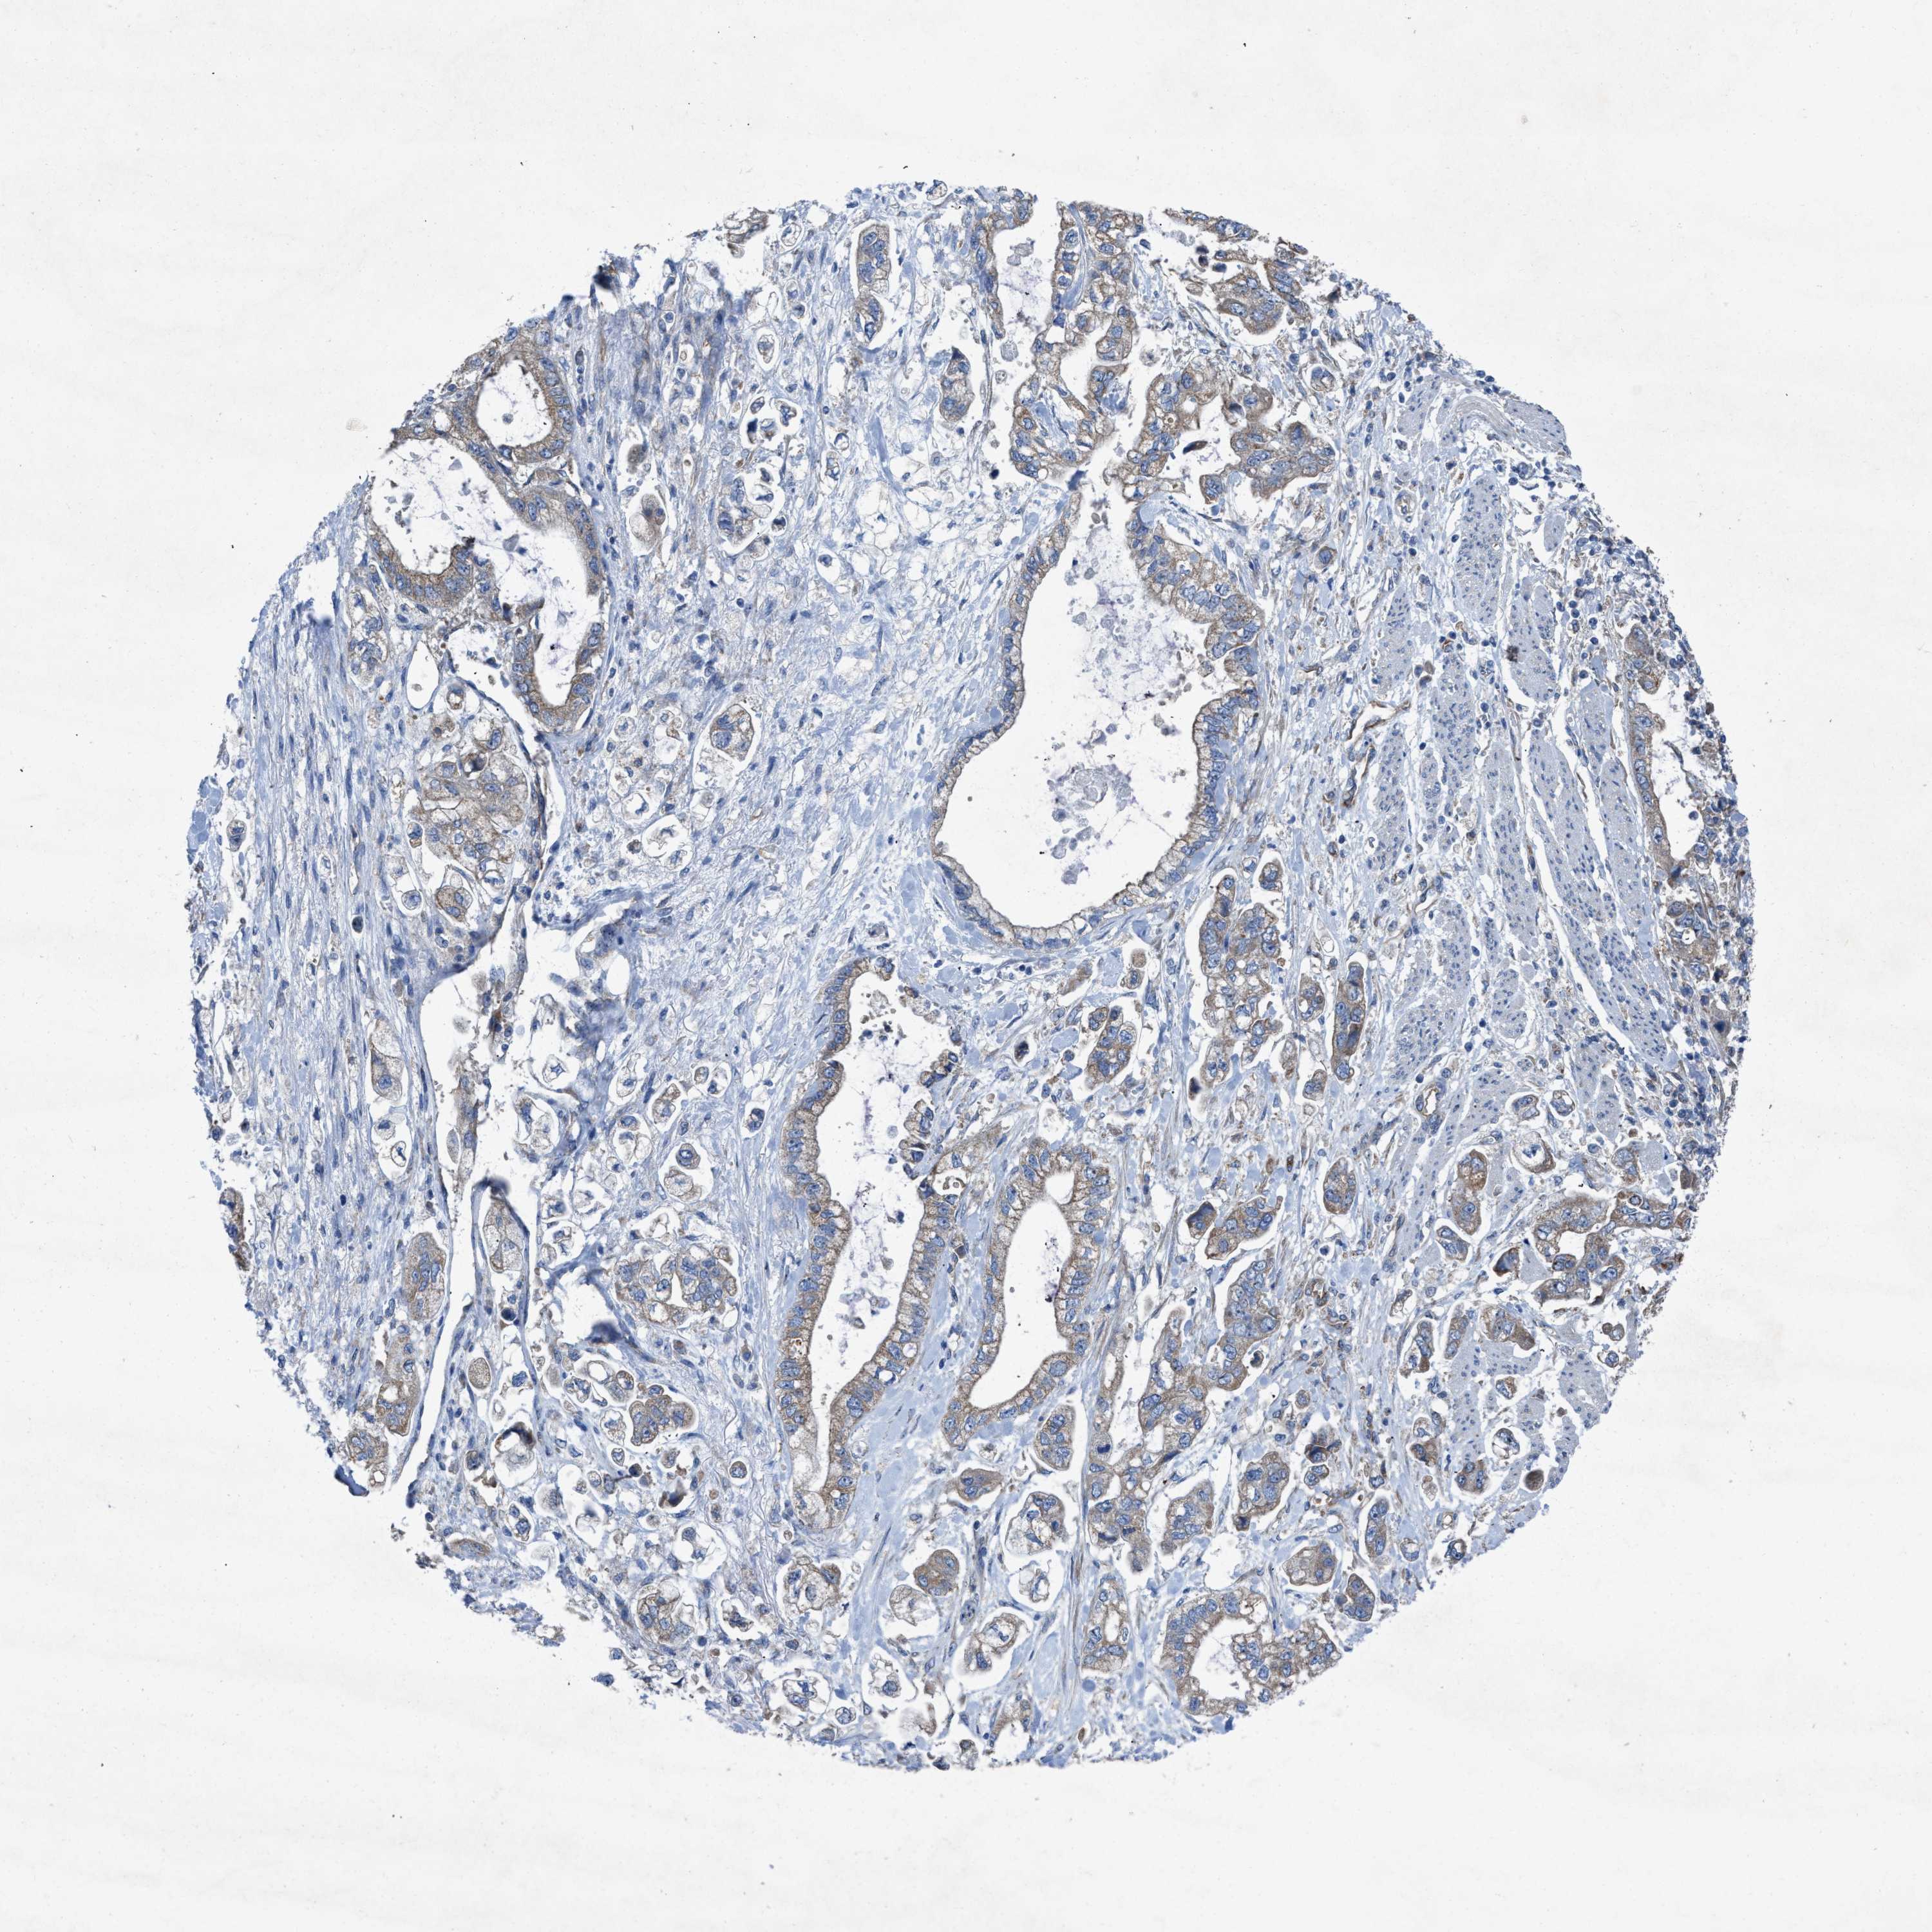

STOMACH CANCER - Protein expressioni

A mouse-over function shows sample information and annotation data. Click on an image to view it in a full screen mode. Samples can be filtered based on level of antibody staining by selecting one or several of the following categories: high, medium, low and not detected. The assay and annotation is described here.

Antibody stainingi

Antibody staining in the annotated cell types in the current human tissue is reported as not detected, low, medium, or high, based on conventional immunohistochemistry profiling in selected tissues. This score is based on the combination of the staining intensity and fraction of stained cells.

Each image is clickable and will lead to virtual microscopy that enables deeper exploration of all samples and also displays staining intensity scores, fraction scores and subcellular localization as well as patient and tissue information for each sample.

Antibody HPA019179

Staining

High

Medium

Low

Not detected

Intensity

Strong

Moderate

Weak

Negative

Quantity

>75%

75%-25%

<25%

None

Location

Nuclear

Cytoplasmic/membranous

Cytoplasmic/membranous,nuclear

Adenocarcinoma, NOS